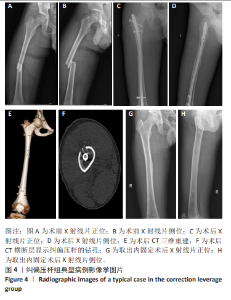

[14] SHUI W, YANG Y, PI X, et al. A novel closed reduction technique for treating femoral shaft fractures with intramedullary nails, haemostatic forceps and the lever principle. BMC Musculoskelet Disord. 2021; 22(1):187.